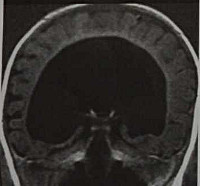

В педиатрии и неонатологии диагностика голопрозэнцефалии не представляет особых затруднений, поскольку даже стертый вариант среднего межполушарного слияния достаточно легко выявить методами современной медицинской визуализации. Нередко это заболевание диагностируется еще на пренатальном этапе при проведении профилактических ультразвуковых исследований (иногда - уже на 12-й неделе беременности). На УЗИ можно отчетливо увидеть аномальное строение черепа и головного мозга плода. При алобарной форме мозг выглядит как наполненный жидкостью пузырь без каких-либо признаков разделения на полушария. Семилобарный тип голопрозэнцефалии характеризуется наличием борозды в задней части мозга, соответствующей неполному или начальному разделению на полушария. Лобарная форма заболевания несколько сложнее обнаруживается при помощи УЗИ, поскольку признаки нарушения разделения мозга фиксируются только в его глубоких слоях - мозолистом теле, таламусе и желудочках.